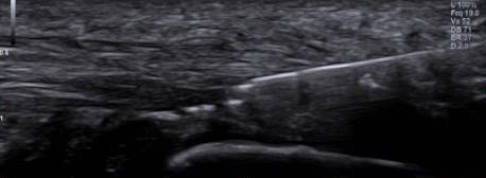

Während der perkutanen Gewebeablation werden alle Schritte des Eingriffs mithilfe eines Ultraschallgeräts überwacht. Vorteil des Ultraschalls ist, dass man damit die Weichteile wie Sehnen und Faszien besser darstellen kann als im Rahmen einer offenen Operation.

Nach lokaler Betäubung führt der Fußchirurg über kleine Hautschnitte spezielle Sonden in das erkrankte Gewebe ein. Auf dem angeschlossenen Monitor sieht er die Sonde ebenso wie die Sehnen oder die Faszienveränderung und kann die bindegewebigen Verdickungen gezielt entfernen. Dadurch reduziert sich die Gewebemenge in der Sehnenplatte, was wiederum den Druck in diesem Bereich der Fußsohle verringert und das Fußgewölbe entlastet. In der Folge verbessern sich bei den meisten Patienten die Schmerzen und Probleme beim Gehen deutlich.